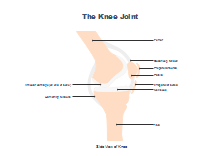

illustrazione scientifica - anatomia umana